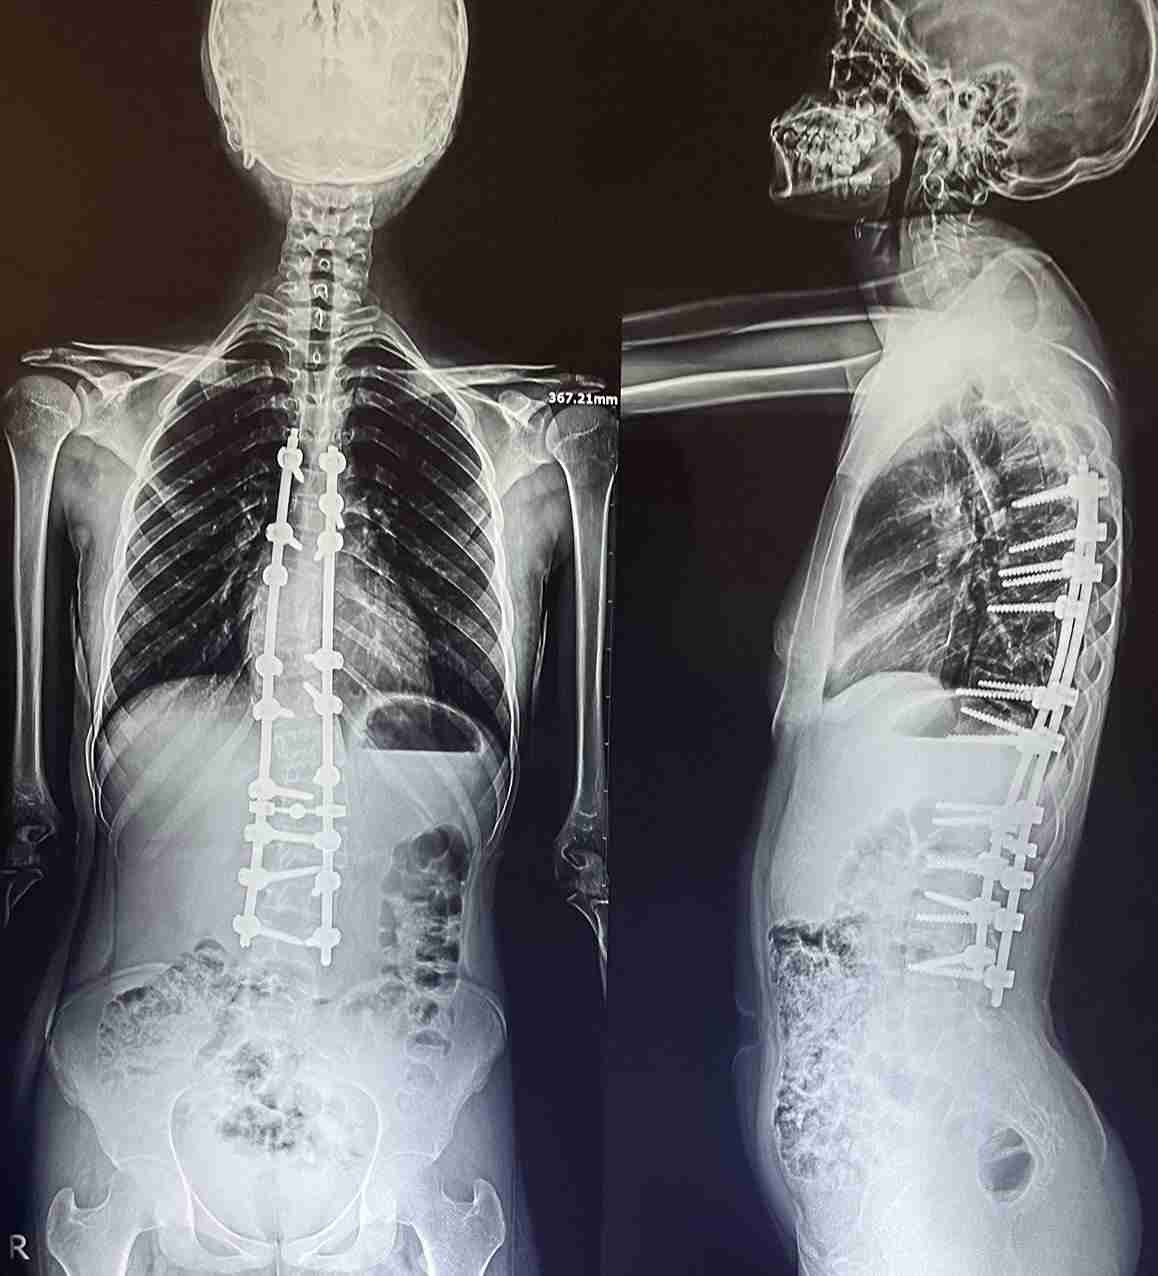

double curvature of the thoracic and lumbar vertebrae

An advanced corrective surgery was performed to treat double curvature in thoracic and lumbar vertebrae. This condition involves abnormal curvatures in both the chest and lower back areas of the spine, affecting posture, movement, and causing chronic pain.

- Correcting double curvatures in thoracic and lumbar vertebrae

- Restoring balance and alignment to the spine

- Use of advanced internal fixation system